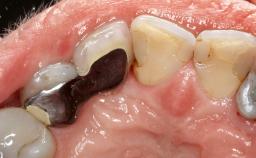

Surgical Management of Peri-Implantitis: Open-Flap Debridement with Seven-Year Follow-up After Treatment

This case describes both a surgical and an anti-infective approach for the management of peri-implantitis, including treatment of the entire dentition to eliminate any deep periodontal pockets that could serve as reservoirs for bacterial re-colonization at the implant site. A 65-year-old female patient was referred to the periodontist in 2013 for assessment and management of an infection at implant 12. On examination, probing depths at implant 12 were 11 mm with suppuration and bleeding on probing.